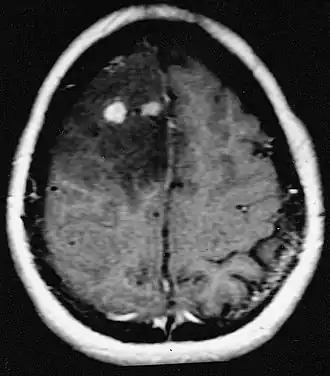

Alla TAC si presenta con una lesione ipodensa e alla RMN come un'area a elevato segnale di intensità in T2. In entrambe le metodiche non viene evidenziato enhancement al mezzo di contrasto.

L'illustrazione a lato mostra un'immagine RM di un astrocitoma diffuso del lobo frontale destro. La neoplasia è in parte di grado II (parte più scura) e in parte di grado elevato (come rappresentato dalle localizzazioni bianche di contrast-enhancing).